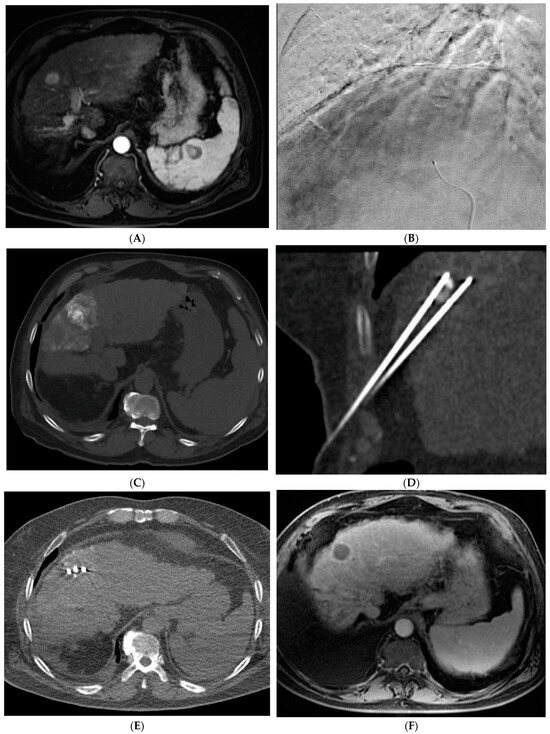

Figure 1. 66-year-old woman with cirrhosis secondary to autoimmune hepatitis and HCC, treated with microwave ablation. (A) Arterial phase MRI showing a 3.5 cm arterially enhancing mass in the periphery of segment 7. (B) Delayed phase MRI demonstrating washout of the mass. Intraprocedural axial (C) and coronal (D) CT images demonstrating probe placement bracketing the mass. (E) Arterial phase MRI one month post ablation showing no residual viable tumor. (F) Arterial phase MRI one year post ablation demonstrating no residual or recurrent viable tumor and involution of the ablation cavity.

Percutaneous ablation is a curative option for patients with very early stage (BCLC 0) or early stage (BCLC A) HCC tumors < 3 cm who are not otherwise candidates for liver transplantation or resection [7]. Various techniques have been developed including RFA, MWA (Figure 1), cryoablation, and irreversible electroporation (IRE). These techniques require the tumor to be in a favorable location with a margin of normal liver tissue between the tumor and a critical structure. RFA is a heat-based technique that was developed alongside the electrocautery knife used by surgeons [8]. RFA involves creating a closed-loop-circuit with an RF electrode, generator, and grounding pads to produce an alternating current that agitates ions in the tissue leading to heat generation [8]. RFA is susceptible to the heat sink effect whereby adjacent vessels can dissipate heat and thus affect the ability to generate the necessary temperature for tumor necrosis, which is one of the pitfalls of this technique [8]. When compared with surgical resection, RFA has demonstrated similar local control and long-term survival with a significantly lower rate of complications as well as a shorter length of hospital stay [18,19,20].

MWA involves producing high frequency oscillating electromagnetic fields which lead to the rapid oscillation of water molecules and the generation of heat. This technique generates heat with a wider zone of the primary heating and is less susceptible to the heat sink effect than RFA. Therefore, higher temperatures can be achieved with a shorter treatment duration, in some cases providing benefit over RFA [8]. MWA has been shown to result in better 5-year survival when compared with RFA for tumors larger than 3.5 cm [21].